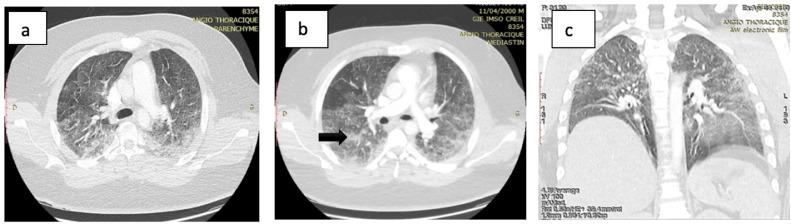

The authors present the case of a young man victim of a traffic accident during the SARS-CoV-2 confinement, having presented a fracture of the femoral shaft that was soon complicated by respiratory failure with oxygen desaturation. In this pandemic context, Covid-19 RT-PCR tests were carried out but returned negative. The CT images could suggest either a fatty embolism, a SARS-CoV-2 infection or both. The patient's condition improved significantly after going into intensive care and only symptomatic treatment. This case demonstrates the difficulty of differential interpretation of CT images between fatty embolism and SARS-CoV-2 infection.

作者介绍了一名年轻男子的病例,该男子在SARS-CoV-2疫情封锁期间遭遇交通事故,出现股骨干骨折,随后很快并发呼吸衰竭和氧饱和度下降。在这种大流行背景下,进行了新冠病毒逆转录聚合酶链反应(Covid-19 RT-PCR)检测,但结果为阴性。CT图像可能提示脂肪栓塞、SARS-CoV-2感染或两者皆有。患者在进入重症监护并仅接受对症治疗后病情显著改善。该病例表明脂肪栓塞和SARS-CoV-2感染在CT图像鉴别诊断上存在困难。